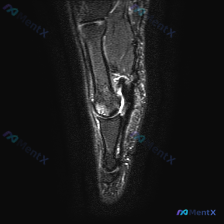

看到这个读片病例,整理了完整的影像分析和诊断思路分享给大家。 病例基本影像信息 这是一幅手部MRI矢状位T2加权图像,显示手指远侧指间关节(DIP)区域: 1. 核心阳性发现:DIP关节间隙内可见明显高信号,提示关节积液,关节间隙增宽,关节囊扩张;关节周围软组织肿胀,背侧及掌侧可见局部高信号影 2....